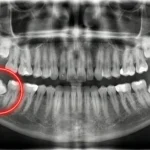

Klasik implant tedavisinde süreç şöyledir: Önce diş çekilir, kemiğin iyileşmesi için 2-3 ay beklenir, ardından implant yapılır ve tekrar beklenir. Bu süreç hastalar için yorucu ve uzun olabilir.

Anında implant tekniğinde ise; çekilmesi gereken diş, çevre kemiğe zarar vermeden hassas bir şekilde çekilir ve aynı seansta, aynı boşluğa hiç vakit kaybetmeden implant yerleştirilir.